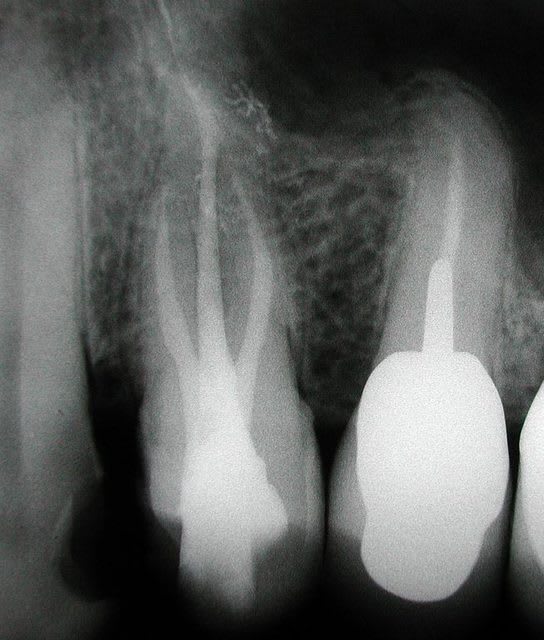

etonnante tout de meme cette 21 et son canal lateral, visiblement il le voulait celui la (ou est ce une image de resorption intra?), s'il l'a vu avant je me demande bien comment il a fait...

y a bien une résorption interne. pj la préop

Dscn5150 jjwlr6 - Eugenol